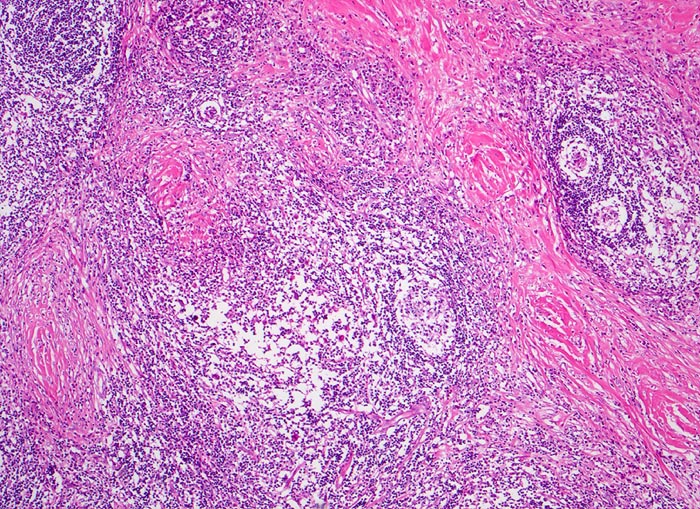

PathoPic – image database / PathoPic ID 3876 - Hodgkin-Lymphom, noduläre Sklerose

Hodgkin-Lymphom, noduläre Sklerose

Zerstörung der regulären Zonierung und Gliederung des Lymphknotens durch bindegewebig abgegrenzte Noduli, die aus einem unterschiedlich zellreichen bunten Infiltrat bestehen.

Die noduläre Sklerose ist ein Subtyp des klassischen Morbus Hodgkin mit Kollagenbändern, die mindestens einen Knoten lymphatischen Gewebes umschliessen. Diese enthalten Hodgkin- und Reed-Sternberg Zellen in Form von Lakunarzellen.